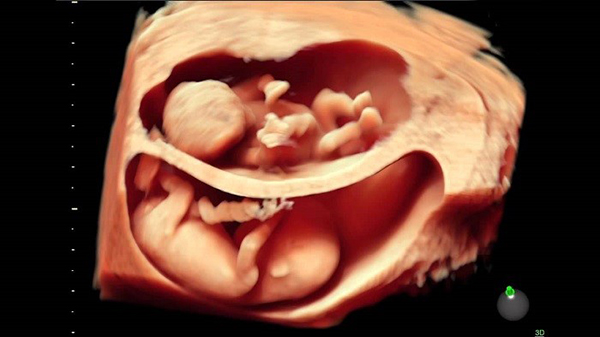

Kích thước phát triển của con trong tuần thứ 7. Kích thước chuẩn cho thai nhi vào tuần 7 là cân nặng khoảng 1gr, chiều dài từ 5-12 mm. Số đo khá nhỏ nên nhìn từ bên ngoài, mẹ sẽ không có sự thay đổi rõ rệt về cơ thể.

Con được 6-7 tuần tuổi, nhịp tim thai rơi vào khoảng trung bình 90-100 lần đập/phút. Bởi tim của bé phải hoạt động liên tục để bơm máu, oxi đi hết cả não, tim và cơ thể. Vì thế có giai đoạn phát triển mạnh, nhịp trung bình sẽ tăng lên đến tận 150-160 lần. phút.